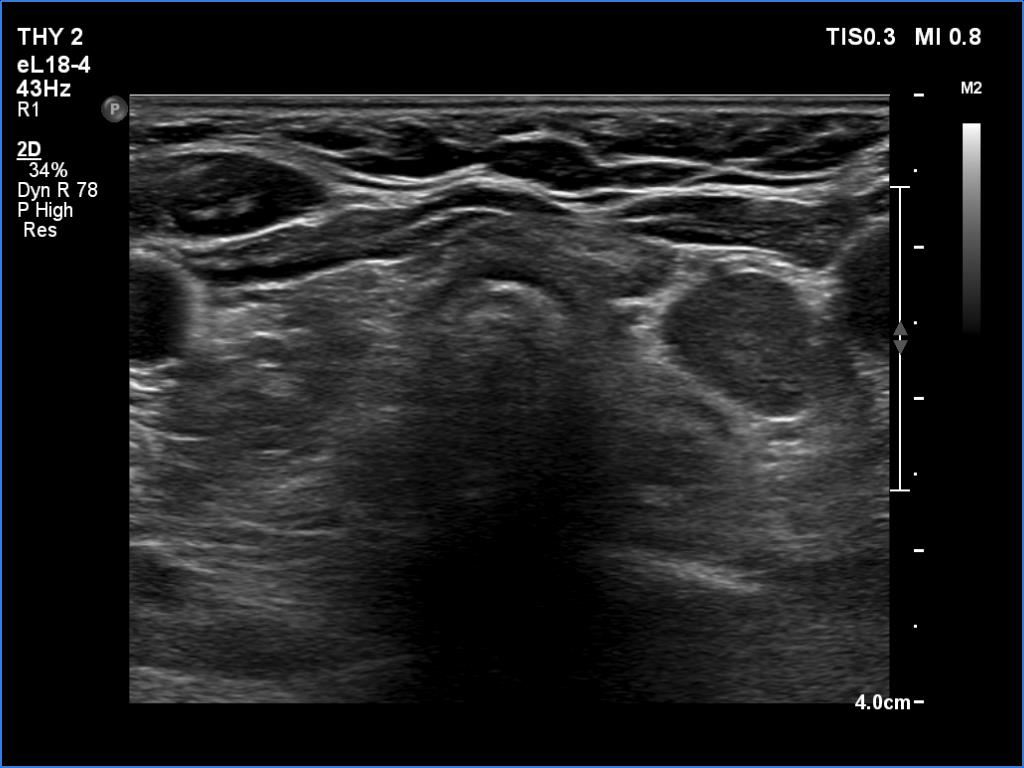

Ultrasonography. The thyroid was atrophic and hypoechoic. There was a hypoechoic mass under the lower pole of the left lobe.